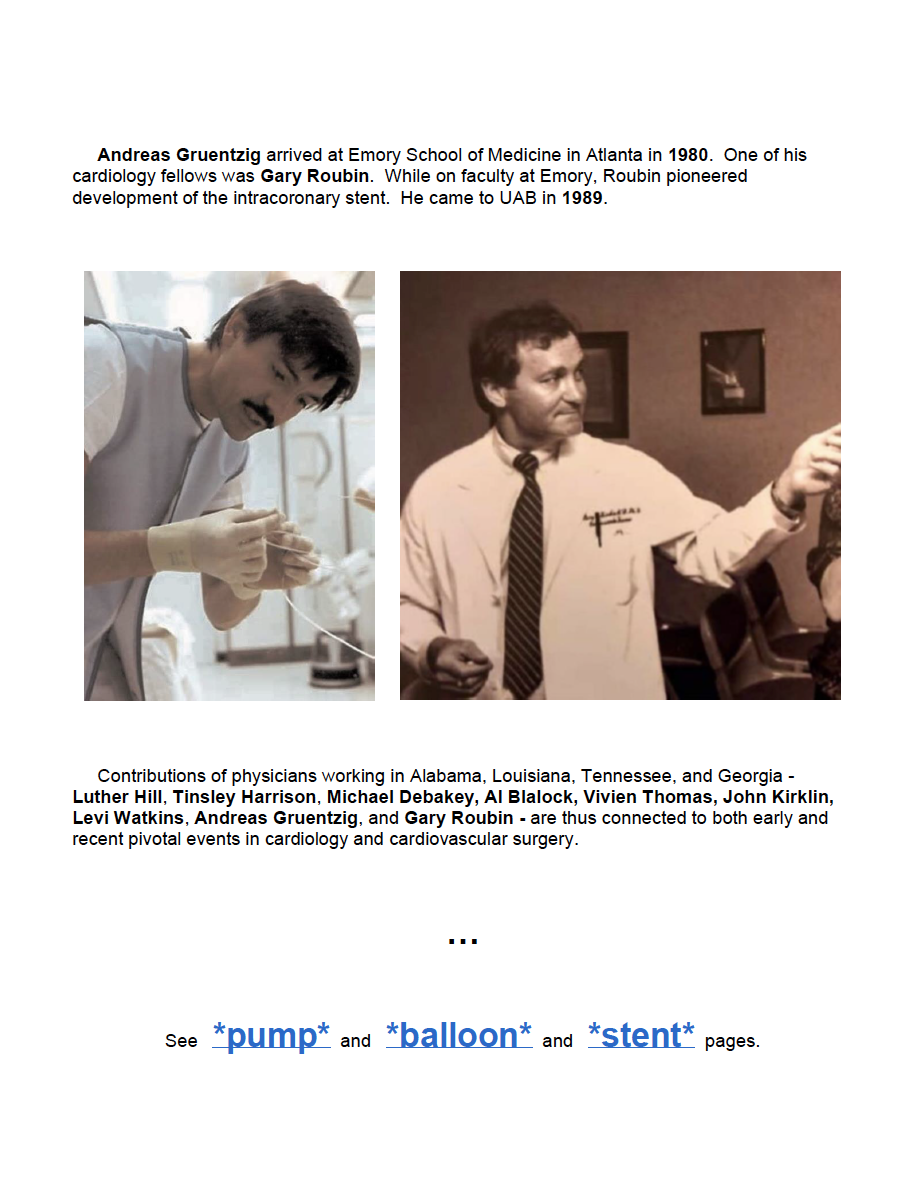

Andreas Grüntzig - 1977: First Coronary Angioplasty - bio - AHA Circulation - 2007

Andreas Gruentzig: The Teaching Genius - article by J. Willis Hurst

The First Balloon-Expandable Coronary Stent - An Expedition That Changed Cardiovascular Medicine - A Memoir - by Gary Roubin - 2015